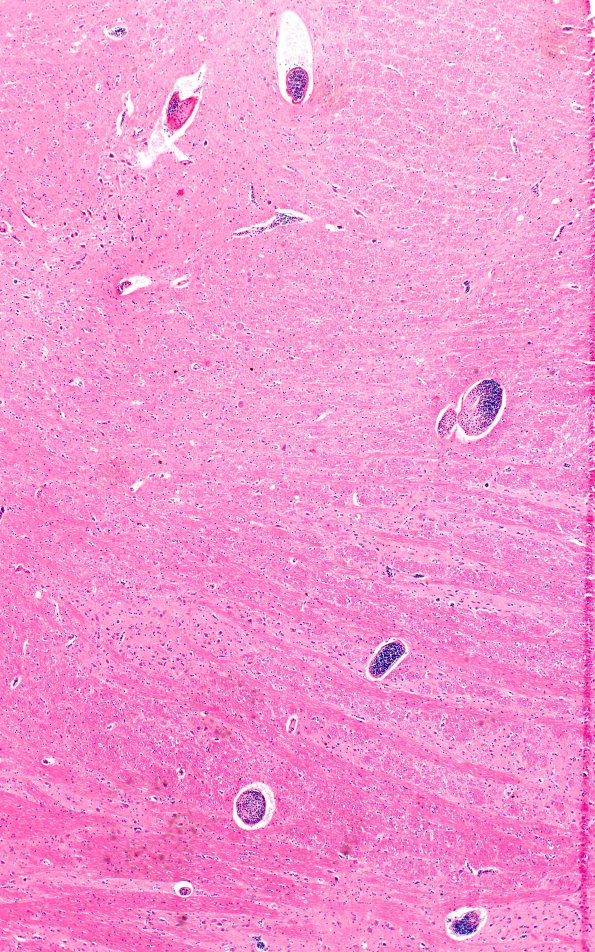

In the pons the leukemic nodules are accompanied by multiple small blood vessels demonstrating leukostasis. (H&E)